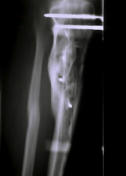

(1998) Bild 1 Komplizierter Splitterbruch vor klinischer Versorgung, Bild 2 vor Therapiebeginn. Bild 3 - 8 Heilungsverlauf.

Bild 1 Komplizierter Splitterbruch vor klinischer Versorgung,

(1998) Bild 1 Komplizierter Splitterbruch vor klinischer Versorgung,